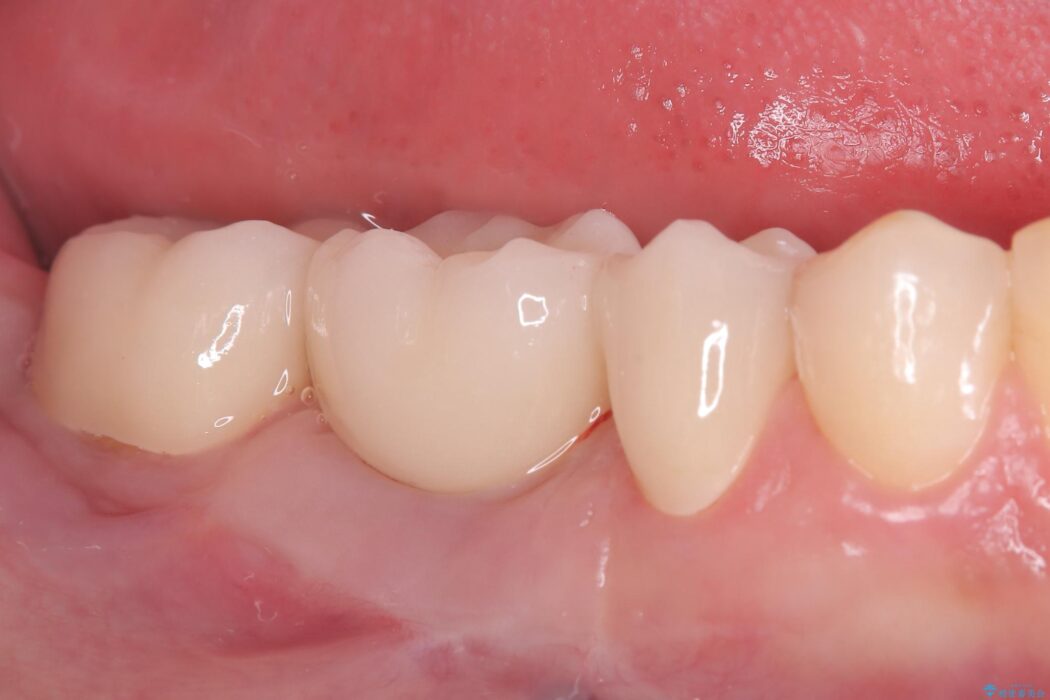

ブリッジを外し、欠損している6番にインプラントを埋入。土台となっていた5番と7番は、セラミッククラウンで修復。

インプラント周囲の歯肉が薄かったため、FGG(遊離歯肉移植術)を行い、長期安定に不可欠な「角化歯肉」を確保しました。

FGG(遊離歯肉移植術)の実施: インプラントを長持ちさせるためには、周囲に硬く動かない「角化歯肉」が必要です。患者様の上あごから丈夫な歯肉を移植するFGGを行うことで、インプラント周囲に十分な厚みと幅のある角化歯肉を形成しました。